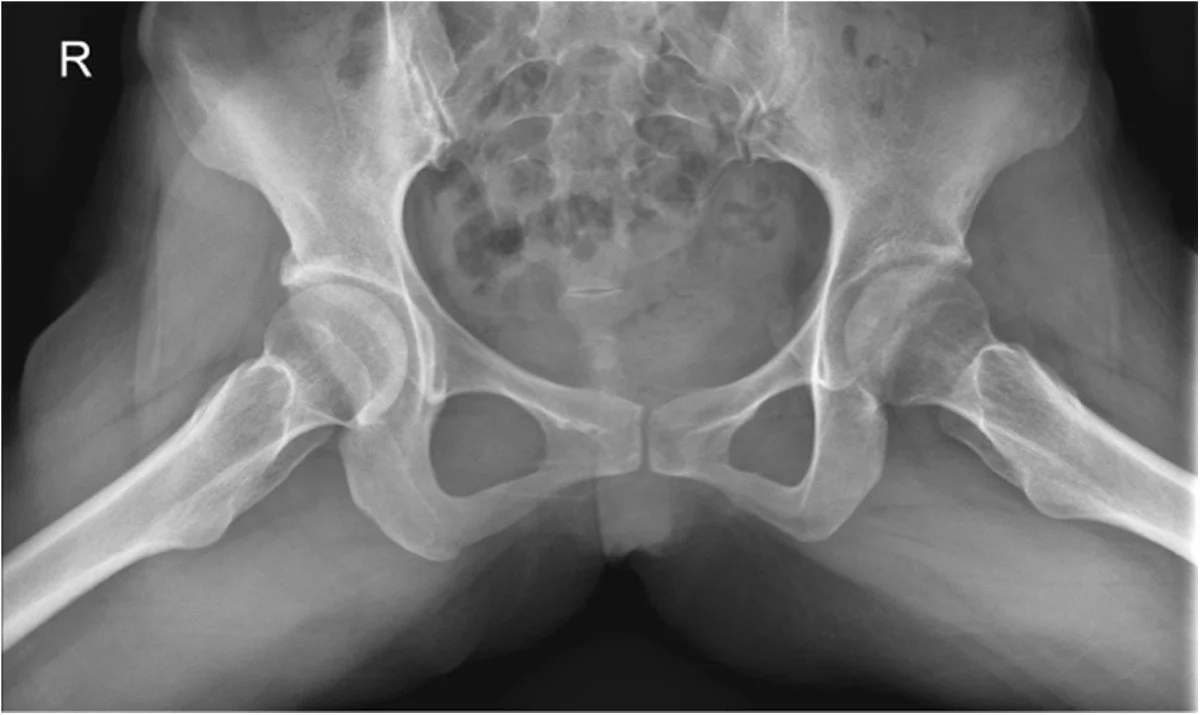

Percentage of professional goaltenders with hip labreal tears and previous or current Hip related injuries

Hip Joint Longevity and Prehab

“I played over 300 professional games in net with two 7+cm tears in my leabreums. Let’s prevent FAI together and manage hip damage so you can have an even longer career than me.

With an emphasis on corrective movements, joint stability and joint mobility we promote healthy biomechanics in the goaltender position to prevent common hip injuries and pathologies in goaltenders like FAI.